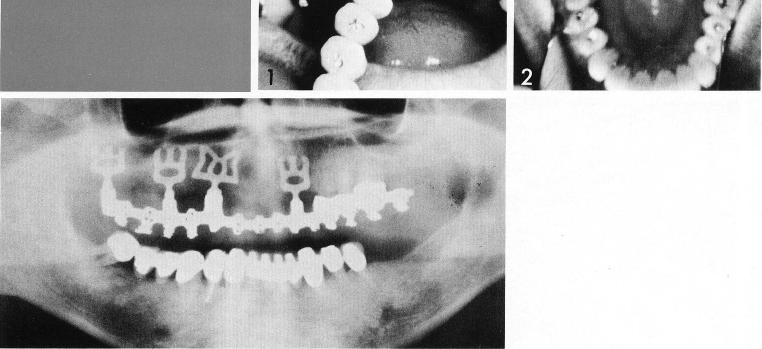

Endosteal blades multiple implant abutments, three teeth remaining

Two single-posted implants often more maximally utilize the available span. Each implant can be seated to take better advantage of the available bone and avoid its flaws.

Endosteal blade

4-unit splint with mid-tooth

support

The single-tooth bladevent here acts as the anterior abutment for a four-unit restoration, preventing the sacrifice of the more anterior crowns for inclusion in the restoration. The single-tooth implant is inserted between a second bicuspid, which has undergone root canal therapy, and the cuspid (1,2). A bladevent is also set behind the natural tooth. Thus three abutments (3) provide strong support for a four-unit restoration (4).

1 Single maxillary tooth implant is inserted in arch

2 Maxillary implant abutments provide support for four unit restoration